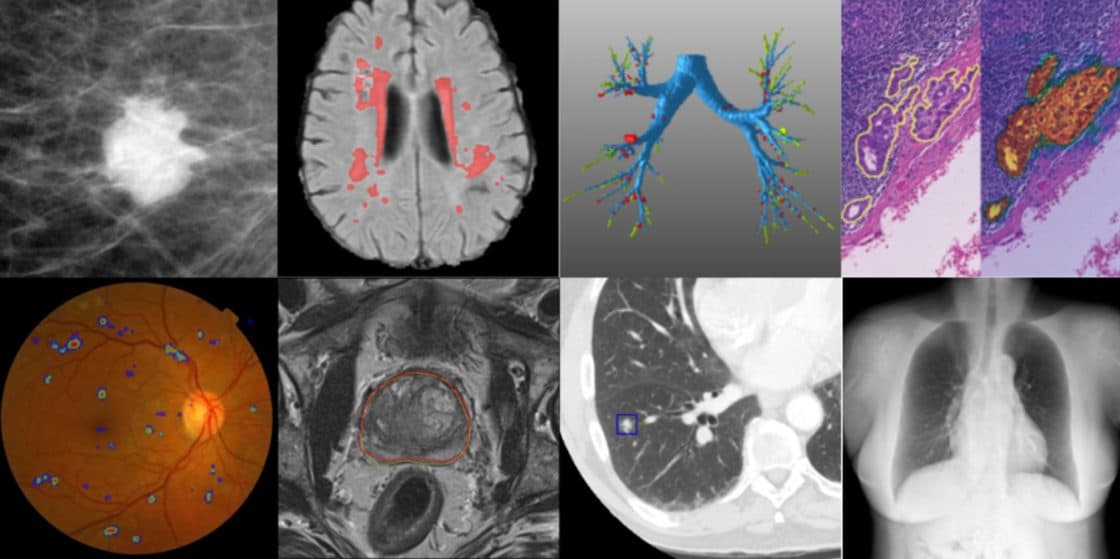

Medical imaging is the process of capturing the structure of an inner organ or tissue. These images can assist medical staff with diagnostics, treatment, and monitoring of patients. It can also prevent any unnecessary invasive procedures.

AI platforms can also detect abnormalities in early stages that in turn enable early treatment and recovery. One of the growing usages of AI is for the purpose of non-invasive radiometric biomarkers. The development of such biomarkers enables us to measure and quantify organs and lesions automatically and compare them to an existing normal database. This allows physicians to accurately and reproducibly monitor the progress of a diagnosis or a given treatment and to avoid, in some cases, the need for an invasive procedure like a biopsy.

In recent years there has been tremendous work in this field mainly focusing on cardiovascular, ophthalmology, neurology, and cancer detection.

In 2016 Google showed higher success in identifying diabetic retinopathy (DR) compared to a group of 7-8 U.S. Board-certified ophthalmologists. Diabetic retinopathy is the fastest growing cause of blindness, with almost half a billion diabetic patients at risk. When not treated this can lead to irreversible blindness. In their research, Google succeeded to train a DCNN (Deep Convolutional Neural Network) for the classification between moderate and worse referable diabetic retinopathy (RDR).

Cancer detection and monitoring is another important application of AI in medical imaging. A pathological report is crucial for an accurate diagnosis and the successful treatment of cancer. The process of examining thousands of 10-megapixel (MP) photos is both time consuming and prone to errors. Liu and Gadepalli had addressed this issue by training an AI (CNN-Inception V3 based) to detect tumors at lesion level. After training several AI models at multiple scales (similar to the way pathologists examine a tissue), the models were able to either match or exceed the performance of a pathologist.